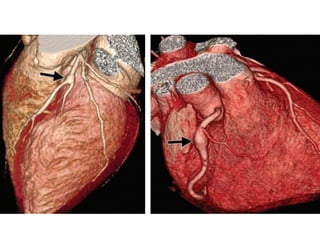

Coronary Aneurysms and Ectasia

Coronary Aneurysms andEctasia • Terminology and Classification • Etiology and pathogeneisis • Examples

Editor's Notes

• #11 1, 2, 3, 19, 61(second from the end)